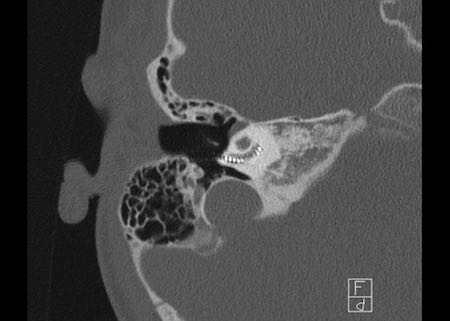

Bên trái là hình ảnh của một nam giới 50 tuổi với nghe kém bên trái.

Có một khối mô mềm kèm ăn mòn mỏm dài xương đe.

Vị trí này điển hình của cholesteatoma pars tensa.